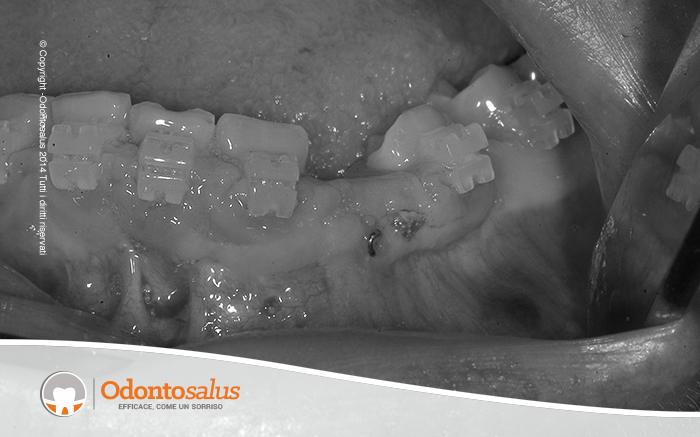

Il canino in questione non si è spostato, pertanto è stato estratto. Il gap dovuto alla sua estrazione è stato riempito con osso prelevato dal mento. Data la favorevole situazione ossea, è stato possibile applicare un impianto, in seguito sepolto per non disturbare la guarigione dell’impianto stesso e dell’osso applicato.

A distanza di circa quattro mesi si è provveduto alla realizzazione e applicazione della corona definitiva su impianto.